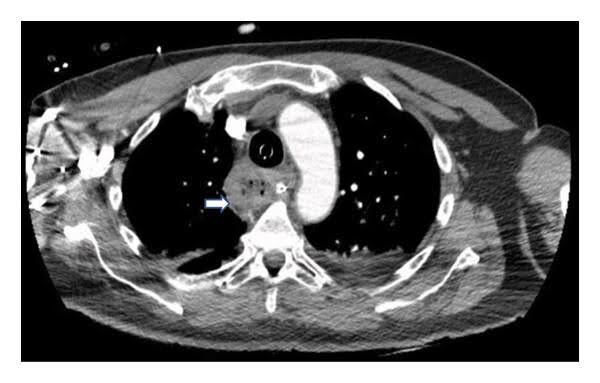

Durch die anschließend durchgeführte Laryngoskopie konnten die Symptome nicht geklärt werden. Mit dieser Untersuchungsmethode ließen sich keine Anomalien darstellen. Mittels der dann durchgeführten Thorax-CT konnte eine Lungenembolie ausgeschlossen werden.1

Abb. 1: CT Thorax1

Hier zeigte sich eine fast vollständige Atelektase des linken Unterlappens und ein aufgeblähter Ösophagus. Der nächste Schritt umfasste eine Magenspiegelung, um der Sache auf den Grund zu gehen.